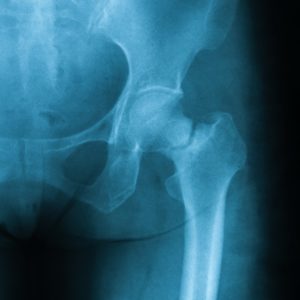

24 hours later, Margaret was wheeled into surgery. A radiology technician had taken an x-ray of her left hip. On the long bone of the thigh (femur), right below the ball that sits in the socket of the hip, was a fracture line. Margaret had broken her hip during the fall and needed a hip replacement as soon as possible.

X-ray image of femoral neck fracture, AP view, showing femoral neck fracture.